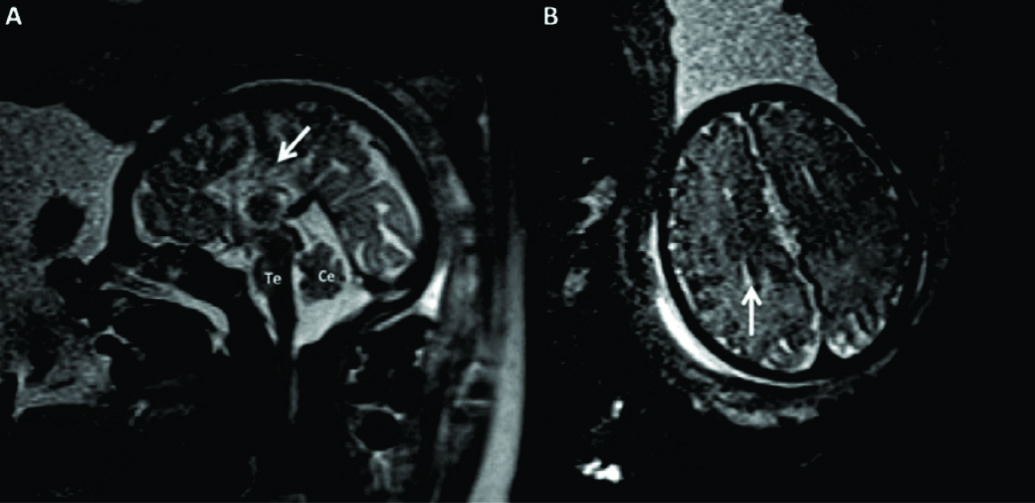

Figura 7

RM Fetal Holoprosencefalia.

RMf a las 28 semanas referido por estudio ecográfico para confirmación de holoprosencefalia. En el plano coronal (A) se identifica la cavidad ventricular única con manto cerebral periférico adelgazado y la característica masa intermedia (MI) por la ausencia de división de ambos tálamos.

En el plano axial (B) los hallazgos son similares con ausencia de estructuras de la línea media como cisura inter-hemisférica u hoz cerebral. Te: Tronco encefálico

Figura 8

RM Fetal Esquizencefalia bilateral.

Estudio de RM realizado en la semana 29 con diagnóstico ecográfico de esquizencefalia bilateral. En el corte axial (A) y coronal (B) se reconocen las clásicas hendiduras que vinculan el sistema ventricular con el espacio sub-aracnoideo de la convexidad en ambos hemisferios.

Las estructuras de línea media son normales así como también el tronco encefálico (Te) y el resto de las estructuras intra-craneanas.